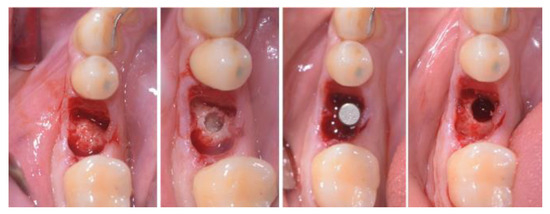

2.3. Treatment Procedure

2.5. Individual Cases Description

3.1. Clinical Results